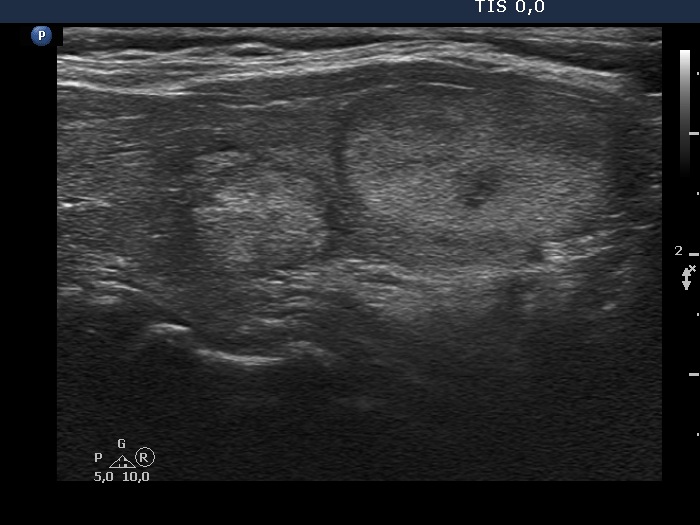

Ultrasonography. The thyroid was moderately hypoechogenic. There were several discrete lesions in the right lobe without any oncological significance. There was a hyperechoic nodule in the lower third of the left lobe, which corresponded to the positive focus on PET CT scan.